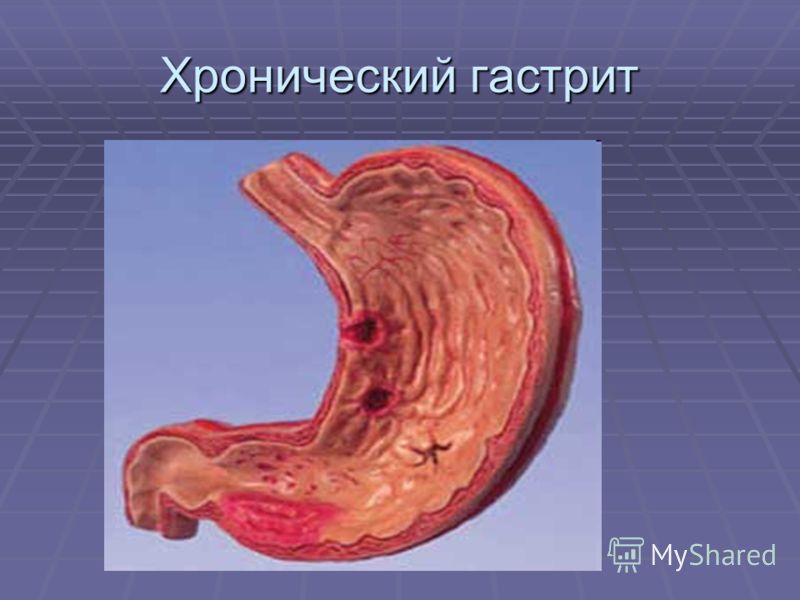

Информация и фотографии о хроническом гастрите и дуодените